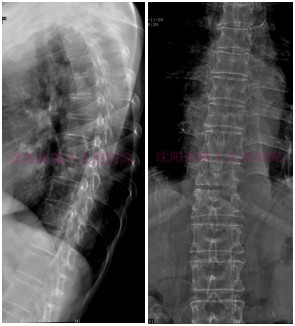

术前DR提示:胸椎轻度侧弯

术前DR提示:胸10-11椎体间隙变窄